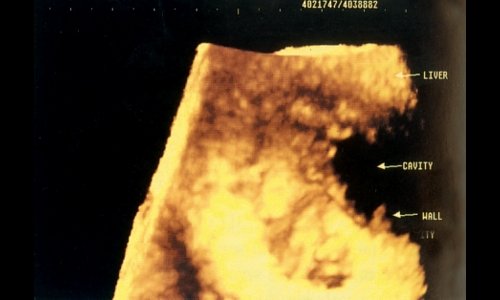

По мнению G. Esmot [16], 3D УЗИ является превосходным методом, позволяющим осмотреть неровную бугристую поверхность печени при циррозе; получаемое изображение при этом весьма сходно с изображением при лапароскопии. Возможно также лоцирование серповидной связки (рис.1) и большого сальника (рис. 2).

Рис. 1. Цирроз печени (неровный край печени, асцит) - круглая связка печени (F.L.) визуализируется между левой и правой долями.